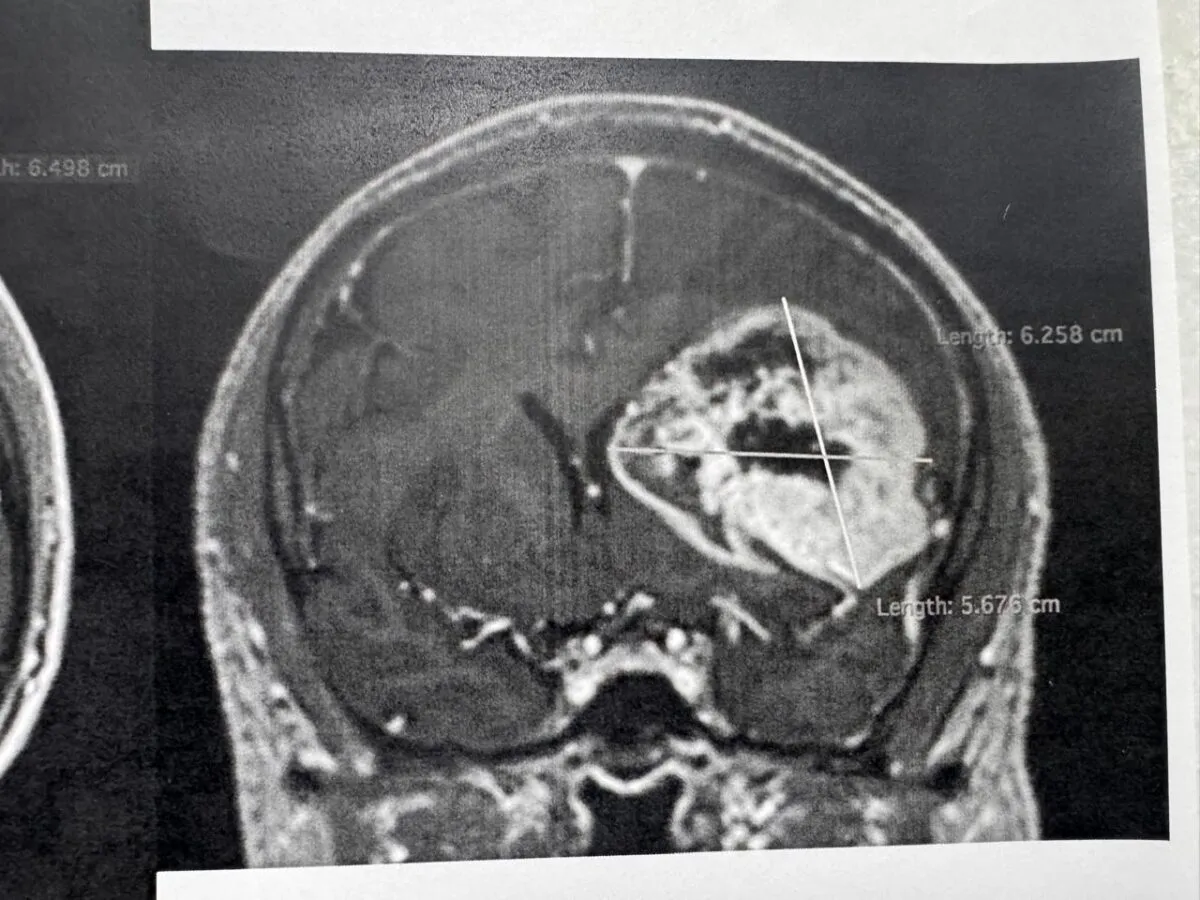

Especialistas en neurología y de diversas áreas retiraron exitosamente un tumor cerebral a un derechohabiente de 54 años, quien permaneció despierto durante el procedimiento que duró siete horas en el Centro Médico (CMN) “20 de Noviembre”, perteneciente al Instituto de Seguridad y Servicios Sociales de los Trabajadores del Estado (ISSSTE), que encabeza el director general Martí Batres Guadarrama.

El neurocirujano a cargo de la operación, Cuauhtémoc Gil Ortiz Mejía, informó que, en coordinación con la especialista en Neuropsicología, se decidió practicarle al derechohabiente un procedimiento llamado craneotomía con paciente despierto, a fin de regresarle las habilidades de lenguaje y motricidad que perdió paulatinamente en un lapso de dos meses por la presencia del tumor.

“El procedimiento realizado en agosto fue de alta complejidad, tuvo una duración de siete horas y se utilizó tecnología de vanguardia, como un neuronavegador cerebral, un microscopio quirúrgico, aspirador ultrasónico, craneotomo eléctrico, neuroestimulador eléctrico de la corteza cerebral, neuromonitoreo transoperatorio y equipo médico de neuroanestesia”, detalló.

Para determinar la realización de este procedimiento y conocer el orígen de los síntomas, explicó, el equipo médico del Instituto le realizó al derechohabiente estudios de tomografía y resonancia magnética.